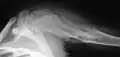

-

X-ray showing enchondromas localized in the humerus of a 37-year-old patient affected with Ollier disease -

Enchondromas localized in the upper part of the humerus of the same patient